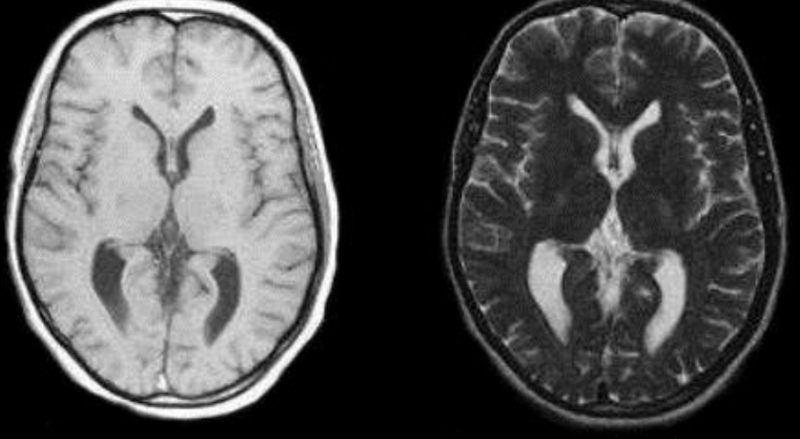

MRI = Magnetic Resonance Imaging

Deze techniek maakt gebruikt van een sterk magneetveld en radiostralen (niet-ioniserend) waarmee organen in het lichaam worden zichtbaar gemaakt. Dit gebeurt echter pixel per pixel, wat dit een heel tijdrovende manier maakt om het lichaam in kaart te brengen.

Hoewel MRI heel goede beeldkwaliteit vertoont en geen ioniserende straling gebruikt, kan men hier een aantal nadelen aan koppelen.

• Door het grote magneetveld dat nodig is, is dit een zeer duur apparaat omdat men nood heeft aan supergeleidende magneten.

• Doordat men pixel per pixel moet opnemen, duurt deze beeldvormingstechniek aanzienlijk langer dan bijvoorbeeld CT

• Patiënten moeten voor lange tijd in een kleine opening liggen, wat voor patiënten met claustrofobie niet aangenaam, of zelfs onmogelijk is.